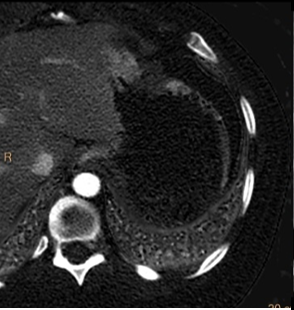

Non-perfused left kidney with transected bowel at ligament of Trietz (red arrow)

Iodine overlay image nicely depicts left kidney injury and bowel injury